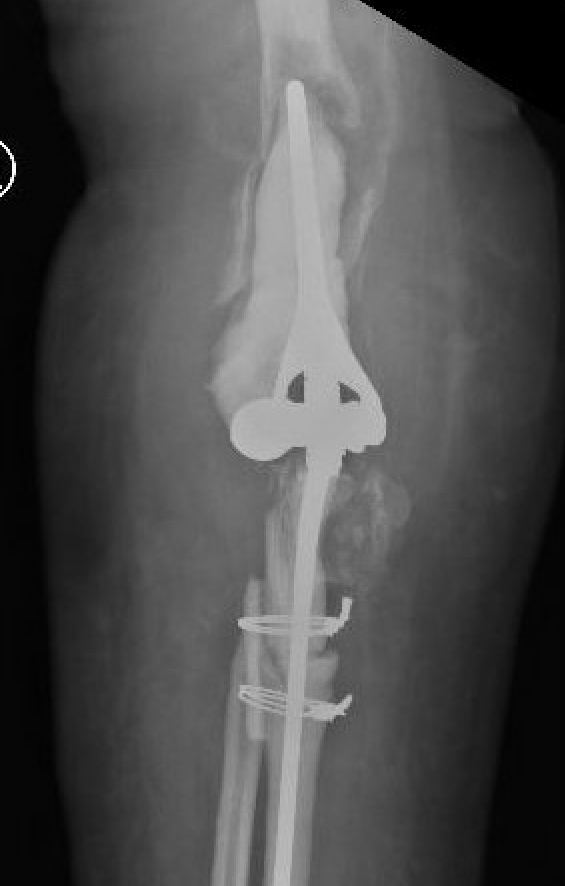

Arthroplasty

1. Size capitellum and trochlea with spool

- insert into olecranon and over radial head

2. Prepare ulna

- resect olecranon fossa

- can remove tip olecranon

- find entry to IM canal & pass IM guide

- prepare canal

- insert trial ulna stem

3. Prepare humerus

- rough cut trochlea

- ensure correct rotation (5 degrees internal rotation)

- use IM rod to attach jig for distal humeral preparation

- release anterior capsule from humerus for anterior flange

- prepare humeral canal

- insert trial humeral stem

4. Trial reduction

5. Insert cement restrictors / implant ulna and humeral prosthesis

6. Insert bone graft under anterior flange

7. Link components

8. Repair collaterals if needed